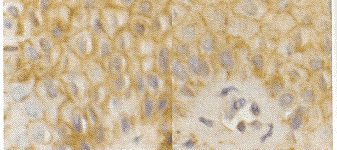

图1 Fas在银屑病恢复期皮损中表达(IH:×40) 图2 FasL在银屑病恢复期皮损中表达(IH:×40)